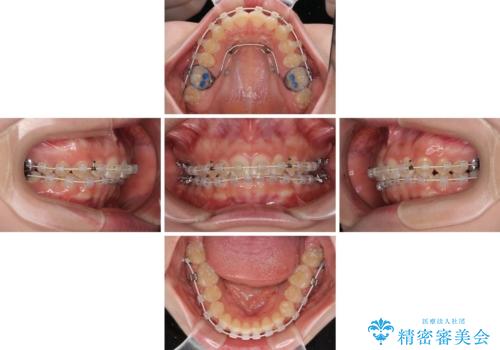

ディープバイトを短期間で改善 ワイヤー矯正治療

- 前歯のデコボコとディープバイトを気にして来院された患者様です。

左上前歯前方に飛び出しているため、歯列全体が前方に移動している状態でした。

短期間で確実に仕上げたいとのことで、アンカースクリューと補助装置を併用して歯列の後方移動を図り、ワイヤー装置にて矯正治療を行うこととしました。

左上の歯列は補助装置により速やかに移動し、1年程度で奥歯の咬み合わせが改善され、1年3ヶ月の短期間でしっかりと仕上げることができました。